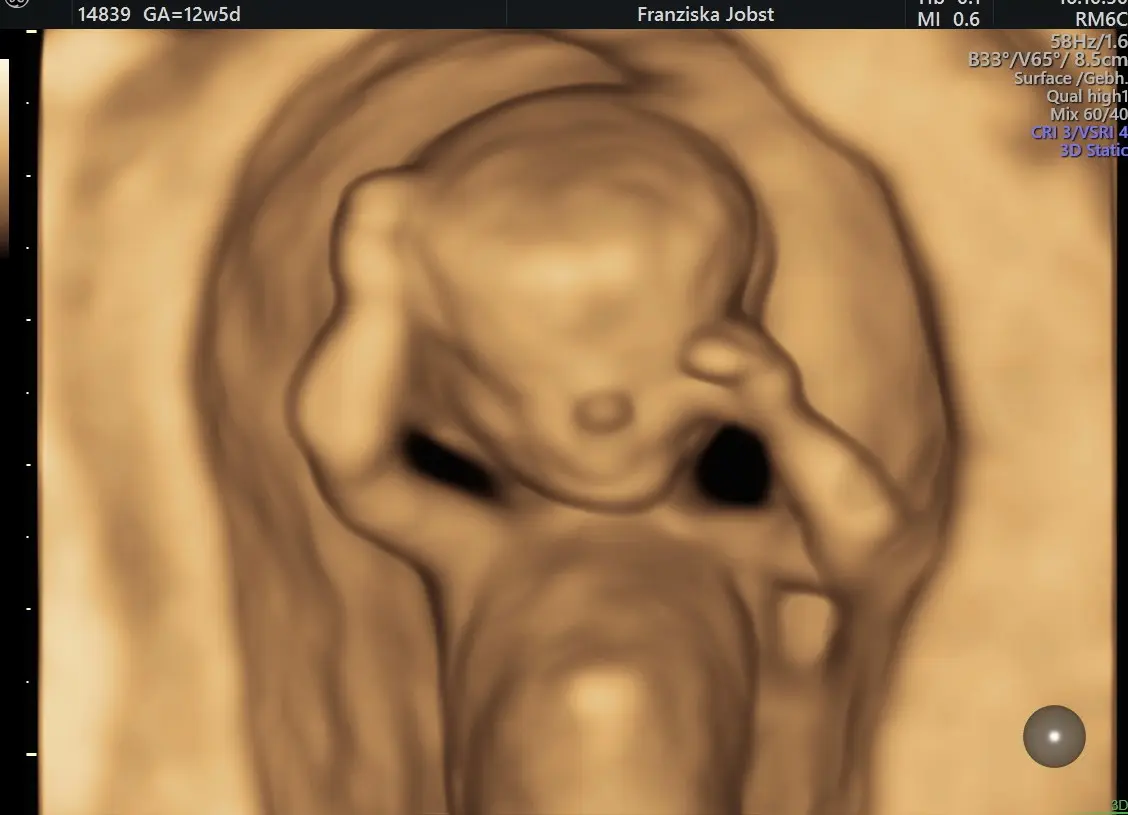

Die Feindiagnostik, auch Fehlbildungsdiagnostik genannt, ist eine spezielle Ultraschalluntersuchung, die während der Schwangerschaft durchgeführt wird. Im Gegensatz zum normalen Ultraschall, der eher einen groben Überblick über die Entwicklung des Fötus gibt, konzentriert sich die Feindiagnostik auf die detaillierte Untersuchung aller wichtigen Organe und Körperstrukturen des Kindes. So können mögliche Fehlbildungen frühzeitig erkannt und gegebenenfalls behandelt werden.

Der optimale Zeitpunkt für die Feindiagnostik liegt zwischen der 20+0 bis 22+6 SSW. In diesem Zeitraum sind die meisten Organe des Fötus ausreichend entwickelt und gut im Ultraschall sichtbar. Die Untersuchung kann aber auch zu einem späteren Zeitpunkt durchgeführt werden, wenn es medizinische Gründe dafür gibt.